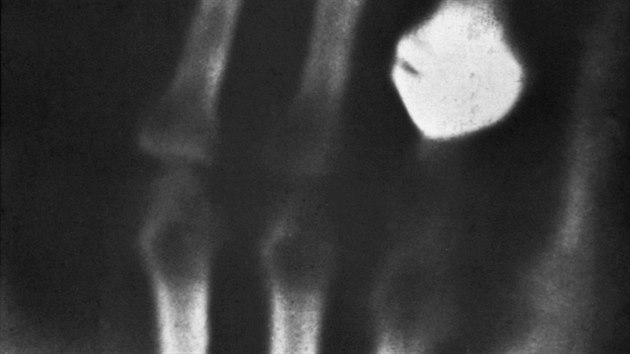

Nazval je „paprsky X“ a pokoušel se je zachytit. Ale jak? V lednu 1896 Röntgena napadlo dát do dráhy paprsků ruku své ženy, za kterou umístil fotografickou desku. Po vyvolání na desce spatřil obraz kostí a prstenu.

Když dnes jdeme na rentgenové vyšetření, lékaři se do nás podívají díky jednoduchému principu. Paprsky o velmi krátkých vlnových délkách, nazvané po panu Röntgenovi, pronikají různými částmi našeho těla různě. Zatímco kosti je pohlcují, svaly a další měkké tkáně je propouštějí. Obraz kostí je tedy na snímku světlejší. Lékař se do nás může podívat i bez skalpelu.